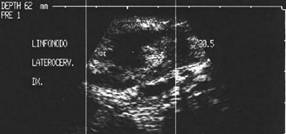

Femeie de 29 ani. Linfonodul in regiunea

laterocervicala dreapta ( 7x12x23mm, 1 cc) in neoplazie papilara a tiroidei. Structura

parenchimatoasa, neomogenea, cu margini

nete, cu absenta hilului.Examen citologic: metastaza de neoplazie papilara.

Lob drept,

proiectie trasversala si longitudinala

Aceeasi pacienta. Nodul de consistenta dura in lobul

drept spre istm.

Ecografia: nodul cu margini indistinte care deformeaza marginea anterioara a glandei,

parenchimatoasa, neomogena, hipoecogena. Prezenta de linfonodi laterocervicali.

Ctoaspiratie: carcinom papilar.